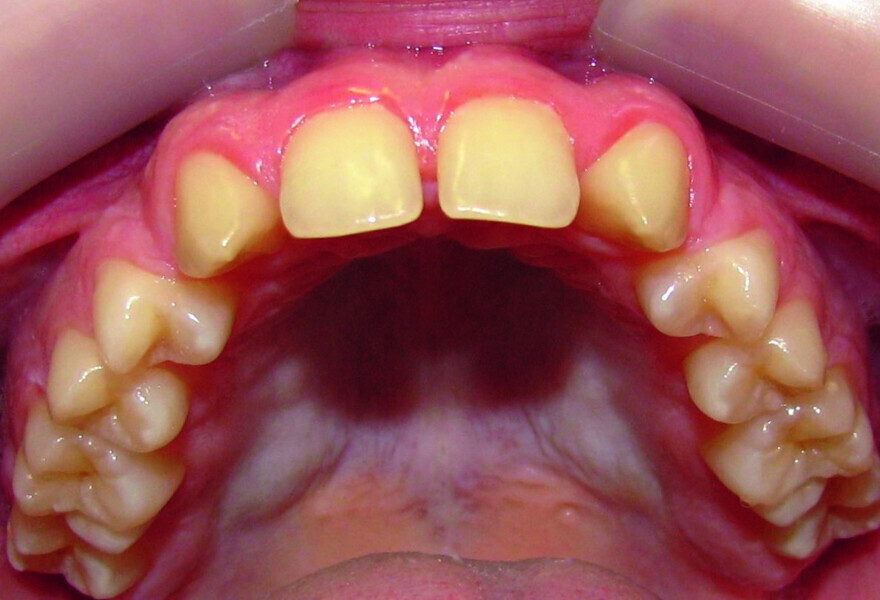

Orthodontic management of maxillary lateral incisors agenesis